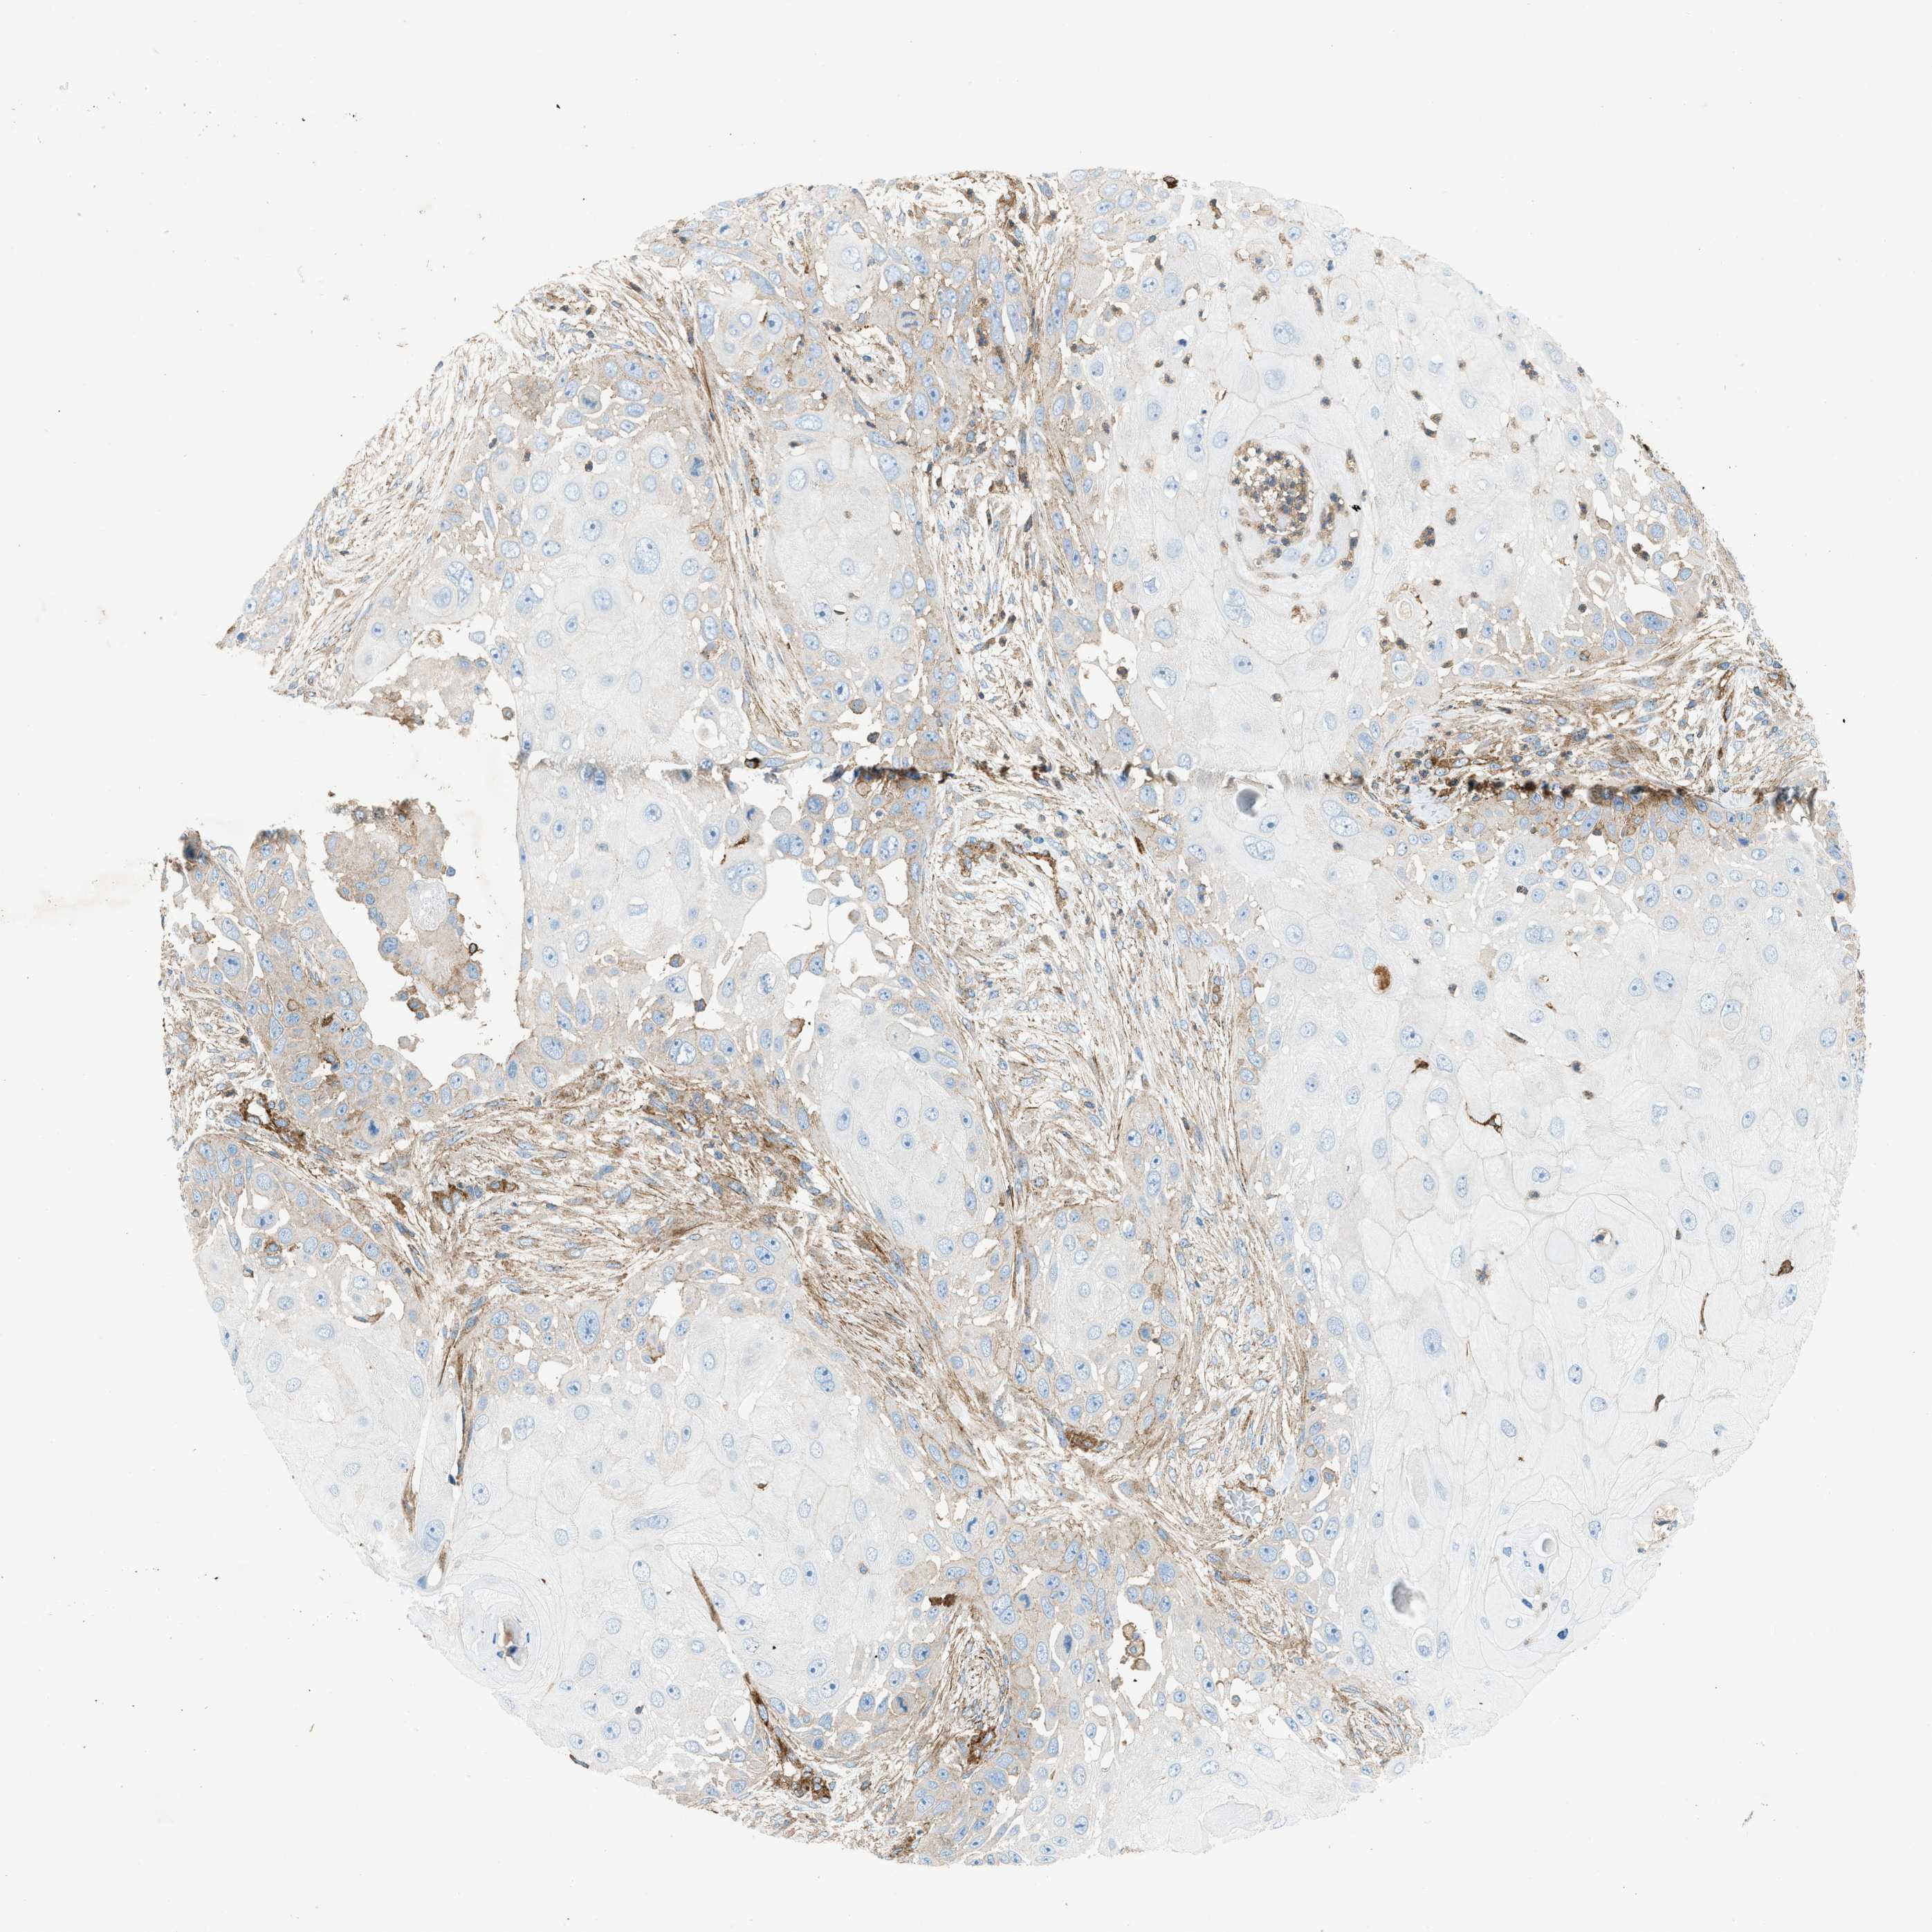

SKIN CANCER - Protein expressioni

A mouse-over function shows sample information and annotation data. Click on an image to view it in a full screen mode. Samples can be filtered based on level of antibody staining by selecting one or several of the following categories: high, medium, low and not detected. The assay and annotation is described here.

Antibody stainingi

Antibody staining in the annotated cell types in the current human tissue is reported as not detected, low, medium, or high, based on conventional immunohistochemistry profiling in selected tissues. This score is based on the combination of the staining intensity and fraction of stained cells.

Each image is clickable and will lead to virtual microscopy that enables deeper exploration of all samples and also displays staining intensity scores, fraction scores and subcellular localization as well as patient and tissue information for each sample.

Antibody CAB016402

Staining

High

Medium

Low

Not detected

Intensity

Strong

Moderate

Weak

Negative

Quantity

>75%

75%-25%

<25%

None

Location

Nuclear

Cytoplasmic/membranous

Cytoplasmic/membranous,nuclear

Squamous cell carcinoma, NOS

Basal cell carcinoma

Adnexal tumor, benign